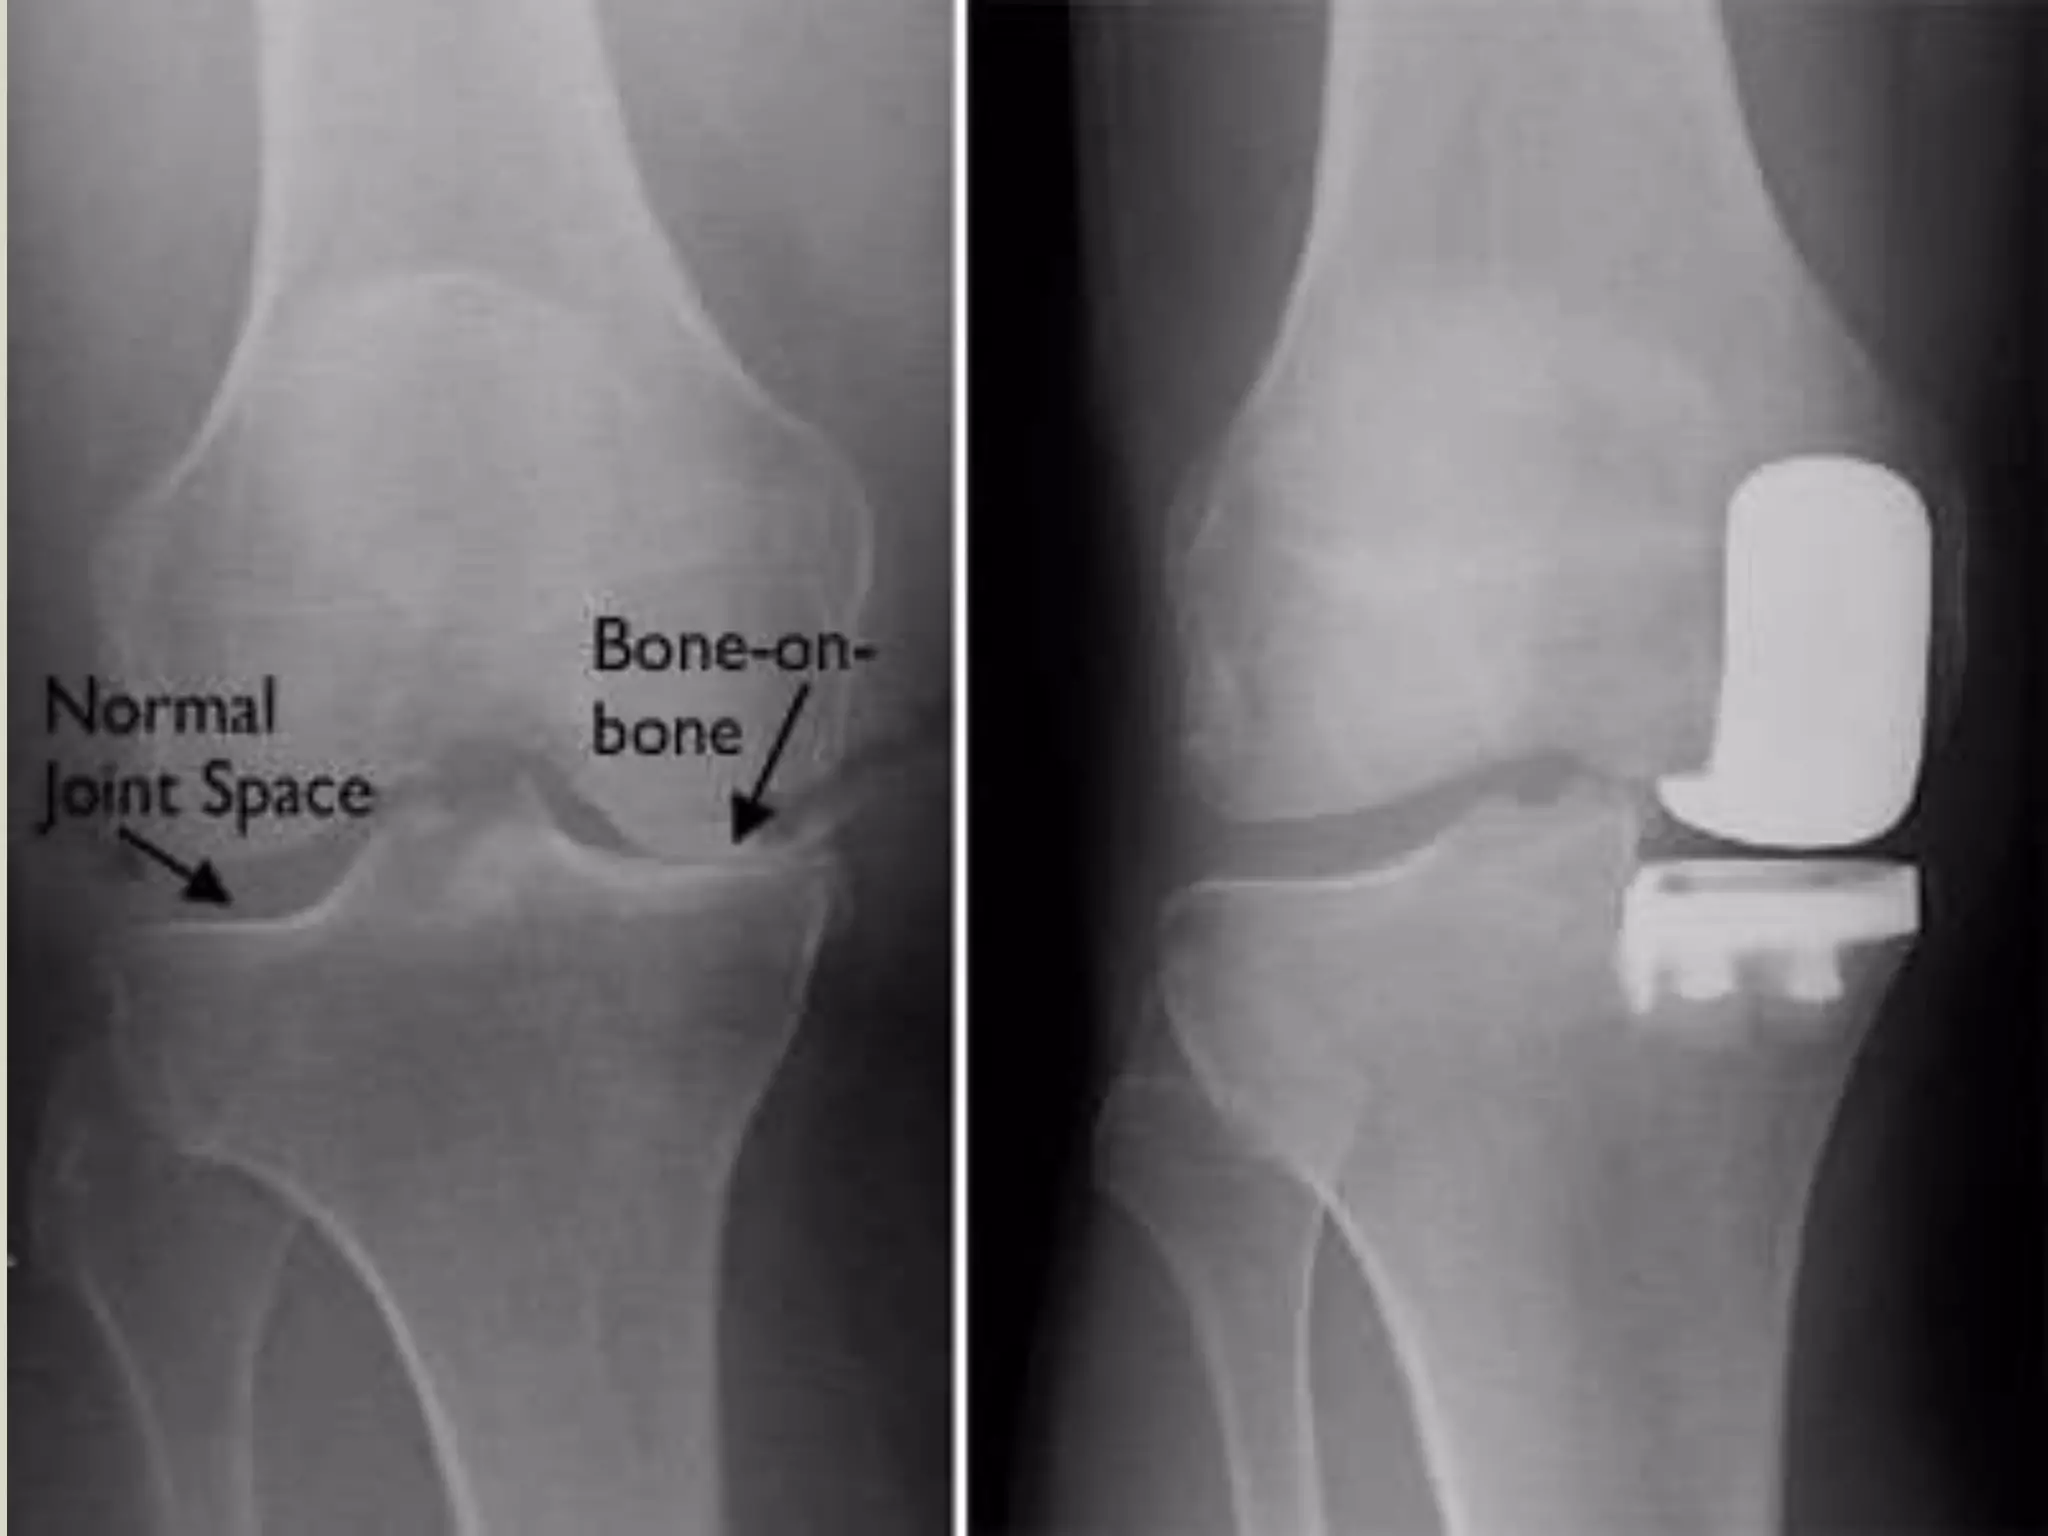

Total Knee

Arthroplasty

Indications for Total Knee

Joint Replacement

The main indication for Total Knee

Arthroplasty is for relief of pain associated

with arthritis of the knee in patients who

have failed non operative treatments.

(American Academy of Orthopedics)

Indications for TotalKnee Joint Replacement The main indication for Total Knee Arthroplasty is for relief of pain associated with arthritis of the knee in patients who have failed non operative treatments. (American Academy of Orthopedics) 38